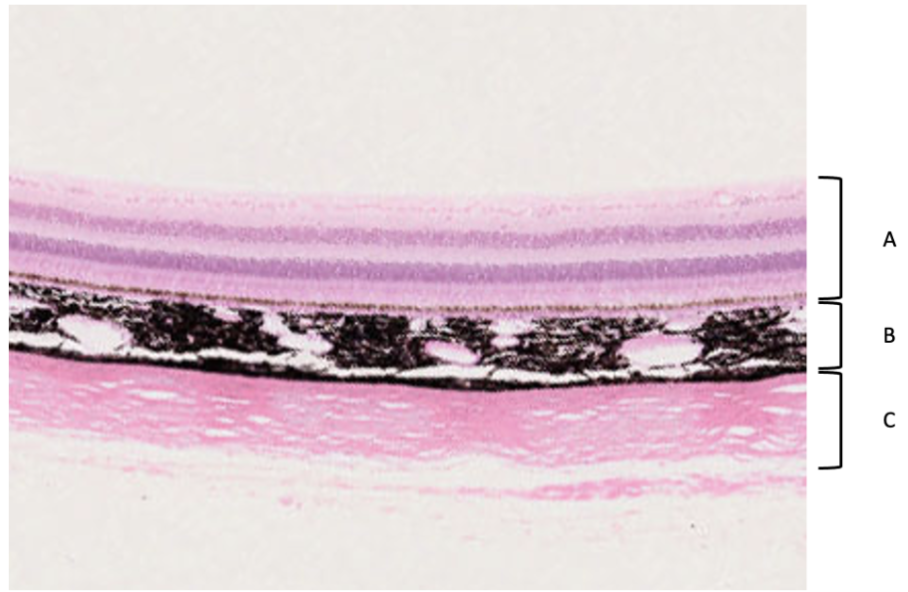

Ögat indelas i tre lager, och bilden visar dessa lager i den bakre delen av ögat (A-C).

a) Om man följer respektive lager mot den anteriora (främre) delen av ögat övergår dessa i olika strukturer. Vilka? Lager A kommer att övergå i epitel

• hornhinna Lager C kommer att övergå i Hornhinna

b) I vilket lager finns muskulatur? (0,5p per rätt svar, totalt 2 p)